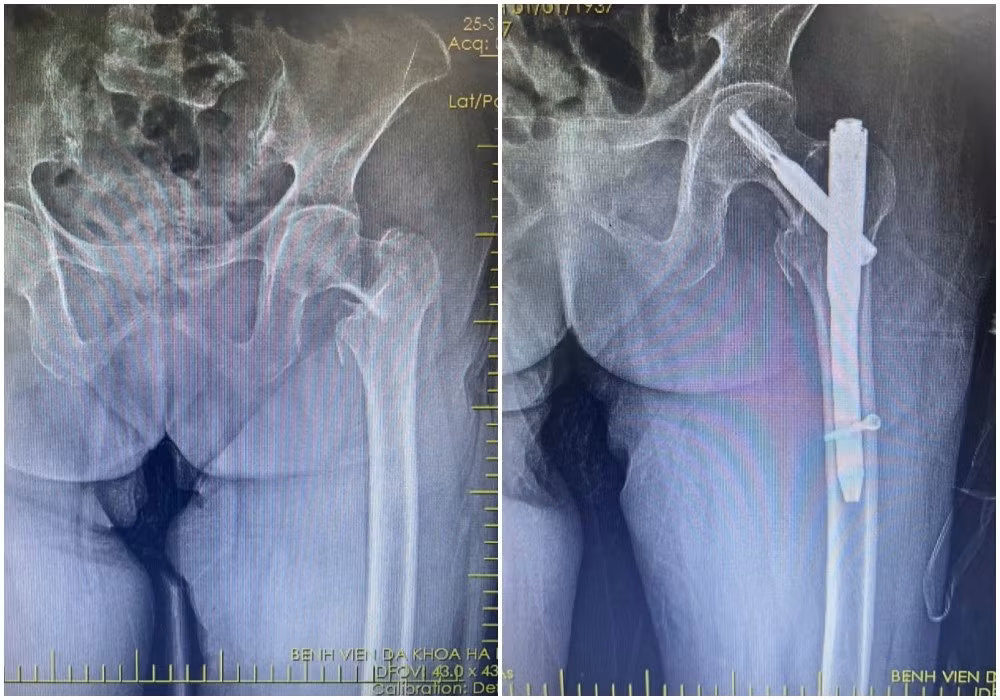

xuong-dui1.jpg

Hình ảnh X-quang gãy liên mấu chuyển xương đùi phải của bệnh nhân N (87 tuổi) được kíp mổ phẫu thuật kết hợp xương ít xâm lấn - Ảnh BVCC

Kết quả chụp X-quang xác định bệnh nhân bị gãy liên mấu chuyển xương đùi. Với tình trạng tuổi cao, sức yếu, việc vận chuyển bệnh nhân hạn chế, tiềm ẩn nguy cơ làm vị trí gãy thêm trầm trọng.

Kíp mổ do bác sĩ CKII Loan Tám Bảy, Phó khoa Chấn thương chỉnh hình phụ trách phối hợp cùng các bác sĩ Bệnh viện Đa khoa Hạ Long thực hiện phẫu thuật kết hợp xương gãy liên mấu chuyển xương đùi bằng phương pháp ít xâm lấn.

Qua đường rạch da nhỏ khoảng 3-5cm, phẫu thuật viên nắn chỉnh xương gãy về vị trí giải phẫu, sau đó cố định bằng đinh nội tủy PFNA dưới màn hình tăng sáng (C-arm).